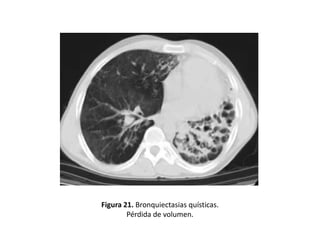

• Otros hallazgos demostrables mediante un estudio

BQ serían: (figuras 19-22).

– Pérdida de volumen o áreas de consolidación

Figura 21. Bronquiectasias quísticas.

Pérdida de volumen.